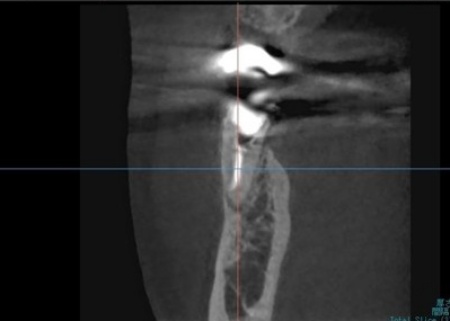

拝見したところ、右下奥歯(第2小臼歯)には保険診療の白い被せ物であるCAD/CAM冠が装着されていましたが、破折して外れている状態でした。

右下奥歯を詳しく検査をした結果、過去に細菌感染した神経を取り除いてから薬を詰める「根管治療」が行われていることがわかりました。

ただ、その手前の右下奥歯(第1小臼歯)では、歯の内部に細菌が侵入して炎症が生じており、歯根の先に膿が溜まる根尖(こんせん)病巣を発症しています。

まず、血液や唾液に含まれる細菌が根管内に入るのを防ぐため、ゴム製のシートであるラバーダムで患部周辺を覆って治療部位だけを露出させ、マイクロスコープで確認しながら感染部位を丁寧に除去しました。

根管内が清潔になったら、再び細菌が入り込まないようにしっかりと薬を詰めて封鎖後、レントゲン撮影で根尖病巣の治癒を確認しました。